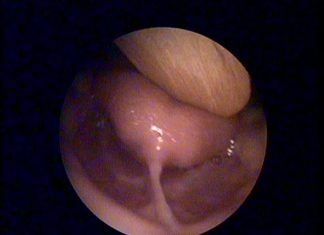

Dil bağı muayenesi nasıl yapılır, dil bağı nasıl farkedilir, dil bağı belirtileri